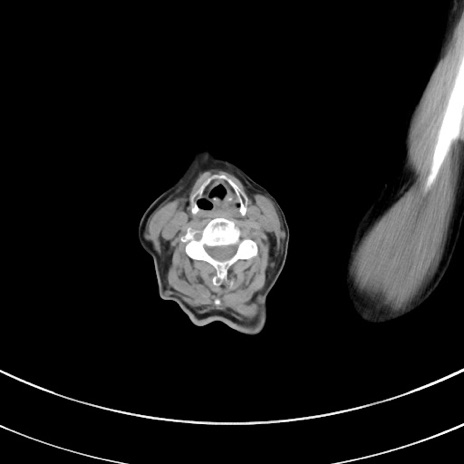

症例33(横断像)

【症例】70歳代 女性

【主訴】心窩部痛

【現病歴】延髄病変の精査・加療にて神経内科入院中。本日より心窩部痛あり。

【既往歴】虫垂炎

【身体所見】右下腹部を中心に圧痛と反跳痛あり。

【データ】WBC 10900、CRP 0.02